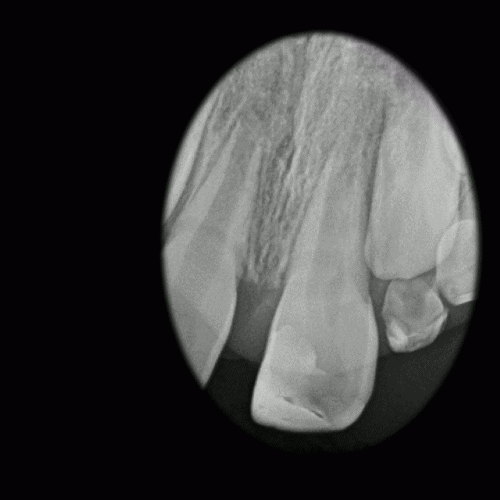

Lid O’er Trash Can – 2 year CBCT recall

By Rajiv Patel / September 4, 2018

Patient presented with a sinus tract -buccal of tooth # 8 History of initial root […]